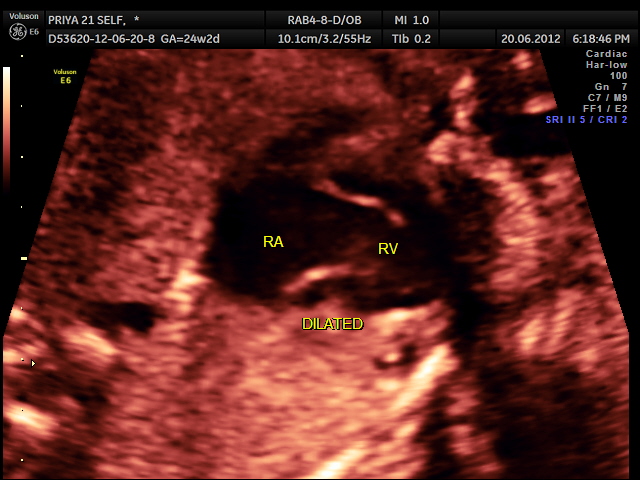

the following video shows right atrium and rt ventricle to be grossly dilated and the left atrium and left ventricle to be very small and hypoplastic.

Hypoplastic left heart syndrome (HLHS) is a severe congenital heart defect in which the left side of the heart is underdeveloped.

- The mitral valve, which separates the two left chambers of the heart, is too small or completely closed (atretic).

- The left ventricle (the lower, pumping chamber) is very small.